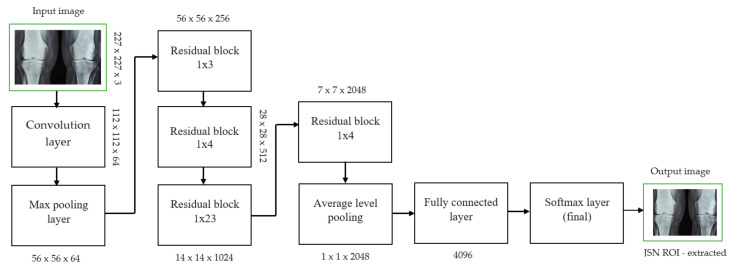

Each convolutional layer in ResNet101 was followed by a batch normalization and activation layer (ReLU). By avoiding parallel connections to the typical layers, this architecture facilitated more efficient training of deep neural networks. Features were extracted, and convolutional feature maps were generated using a combination of convolutional and max-pooling layers. Image characteristics were fed into ERPN, and region suggestions were generated as outputs. The ROI pooling layer took the feature vectors from the function maps. Each vector function was linked to the underlying layer. We individually trained the ROI detection model for the AP view’s medial and lateral compartments. When the algorithm produced several ROI detections, we chose the ROI with the highest prediction accuracy for each knee joint. To evaluate the proposed model, we counted the narrow regions of the marginal joint space that achieved IoU ≥ 0.70. As a result of the detection, we saved the predicted bounding boxes. We used weights that had already been trained on ResNet-101, and then used the domain adaptation method to fine-tune them. Figure 2 shows how modified ResNet-101 can find approaches with a narrow joint space in the knee. The most important part of the Faster R-CNN architecture is ERPN. ERPN predicts the scores of objects and their locations. The algorithm compares the narrow areas of the knee joint space in the medial and lateral compartments to find the narrow area in the middle. The best thing about this method is that it can find even the smallest changes in knee joint space.